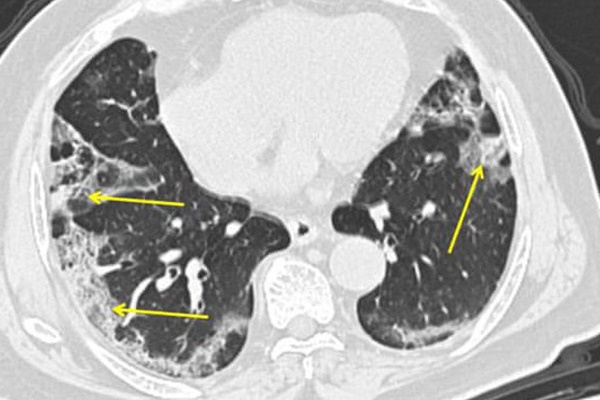

Qua kết quả xét nghiệm, chụp cắt lớp vi tính phổi kiểm tra, các bác sĩ chẩn đoán bệnh nhân bị viêm phổi nặng, biến chứng ARDS, suy hô hấp, nhiễm khuẩn huyết, suy đa tạng, hình ảnh chụp cắt lớp vi tính ngực tổn thương mờ lan tỏa toàn bộ trường phổi hai bên.